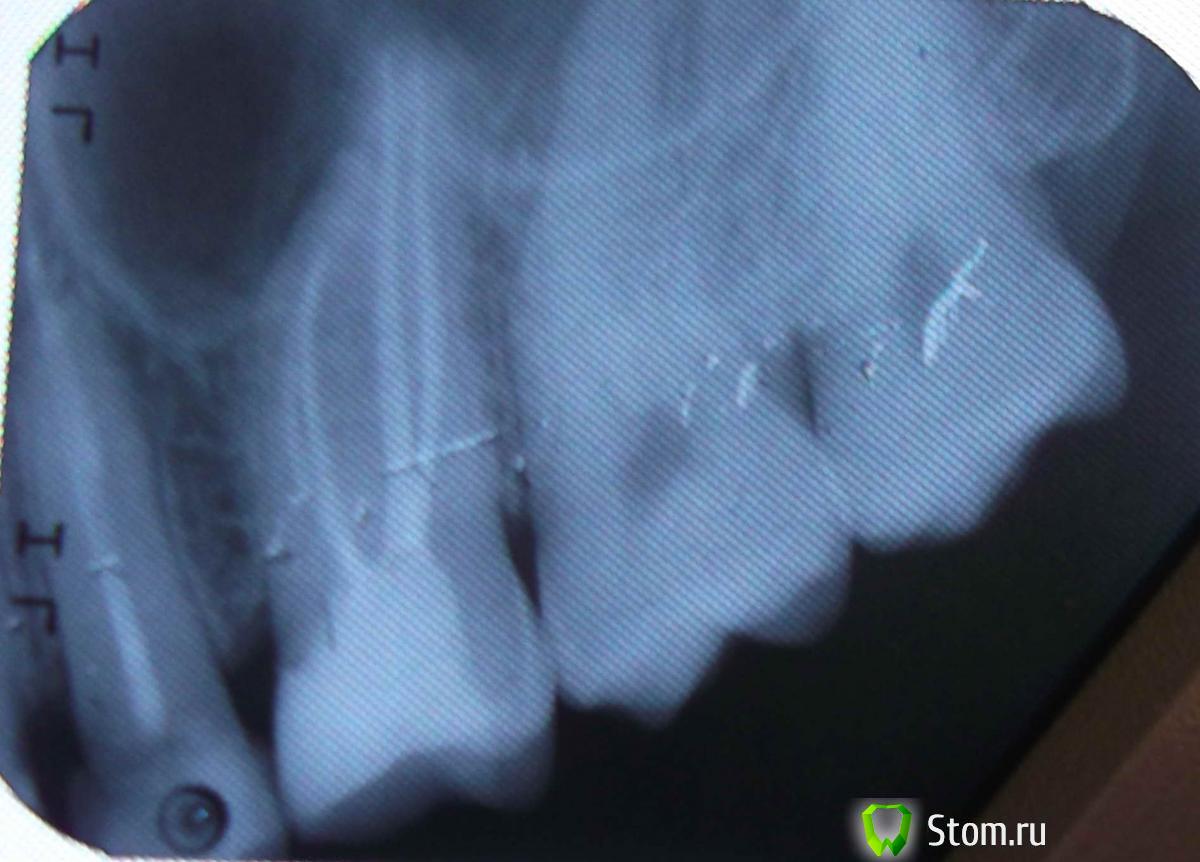

Constantin Опубликовано 30 марта, 2012 Поделиться Опубликовано 30 марта, 2012 Здравствуйте.Нужна консультация по следующему вопросу.Скололась часть пломбы на верхней 5-ке справа.В своё время у этого зуба откололась стенка, скол был под десну.Тогда зуб мне восстановили пломбой и стекловолоконным штифтом.В нынешней ситуации пломбу уже ставить не хотят и отправляют к ортопеду.Был на консультациях в разных клиниках и мнения ортопедов разделились.Первый советует что лучше уже ничего с этм зубом не делать так он дольше прослужит.Второй советует попоробовать поставить пломбу или удалить т.к. коронку ставить не на что,а вкладка в 5-ке плохо держится поэтому он этим заниматься не будет.Третий врач говорит что поскольку в одном канале штифт который вынуть не удасться можно безпроблем поставим вкладку во второй канал и установить коронку. Что посоветуете уважаемые доктора? Спасибо. Ссылка на комментарий

FBR Опубликовано 31 марта, 2012 Поделиться Опубликовано 31 марта, 2012 Удаление штифта. Восстановление культевой вкладкой. Металлокерамическая коронка. И обратите внимание на 16 зуб - его надо перелечивать, т.к. на медиальном корне- гранулема (воспаление). Ссылка на комментарий

FBR Опубликовано 31 марта, 2012 Поделиться Опубликовано 31 марта, 2012 (изменено) Удаление штифта. Восстановление культевой вкладкой. Металлокерамическая коронка. И обратите внимание на 16 зуб - его надо перелечивать, т.к. на медиальном корне- гранулема (воспаление).Пардон - на 46 зуб Изменено 31 марта, 2012 пользователем FBR Ссылка на комментарий